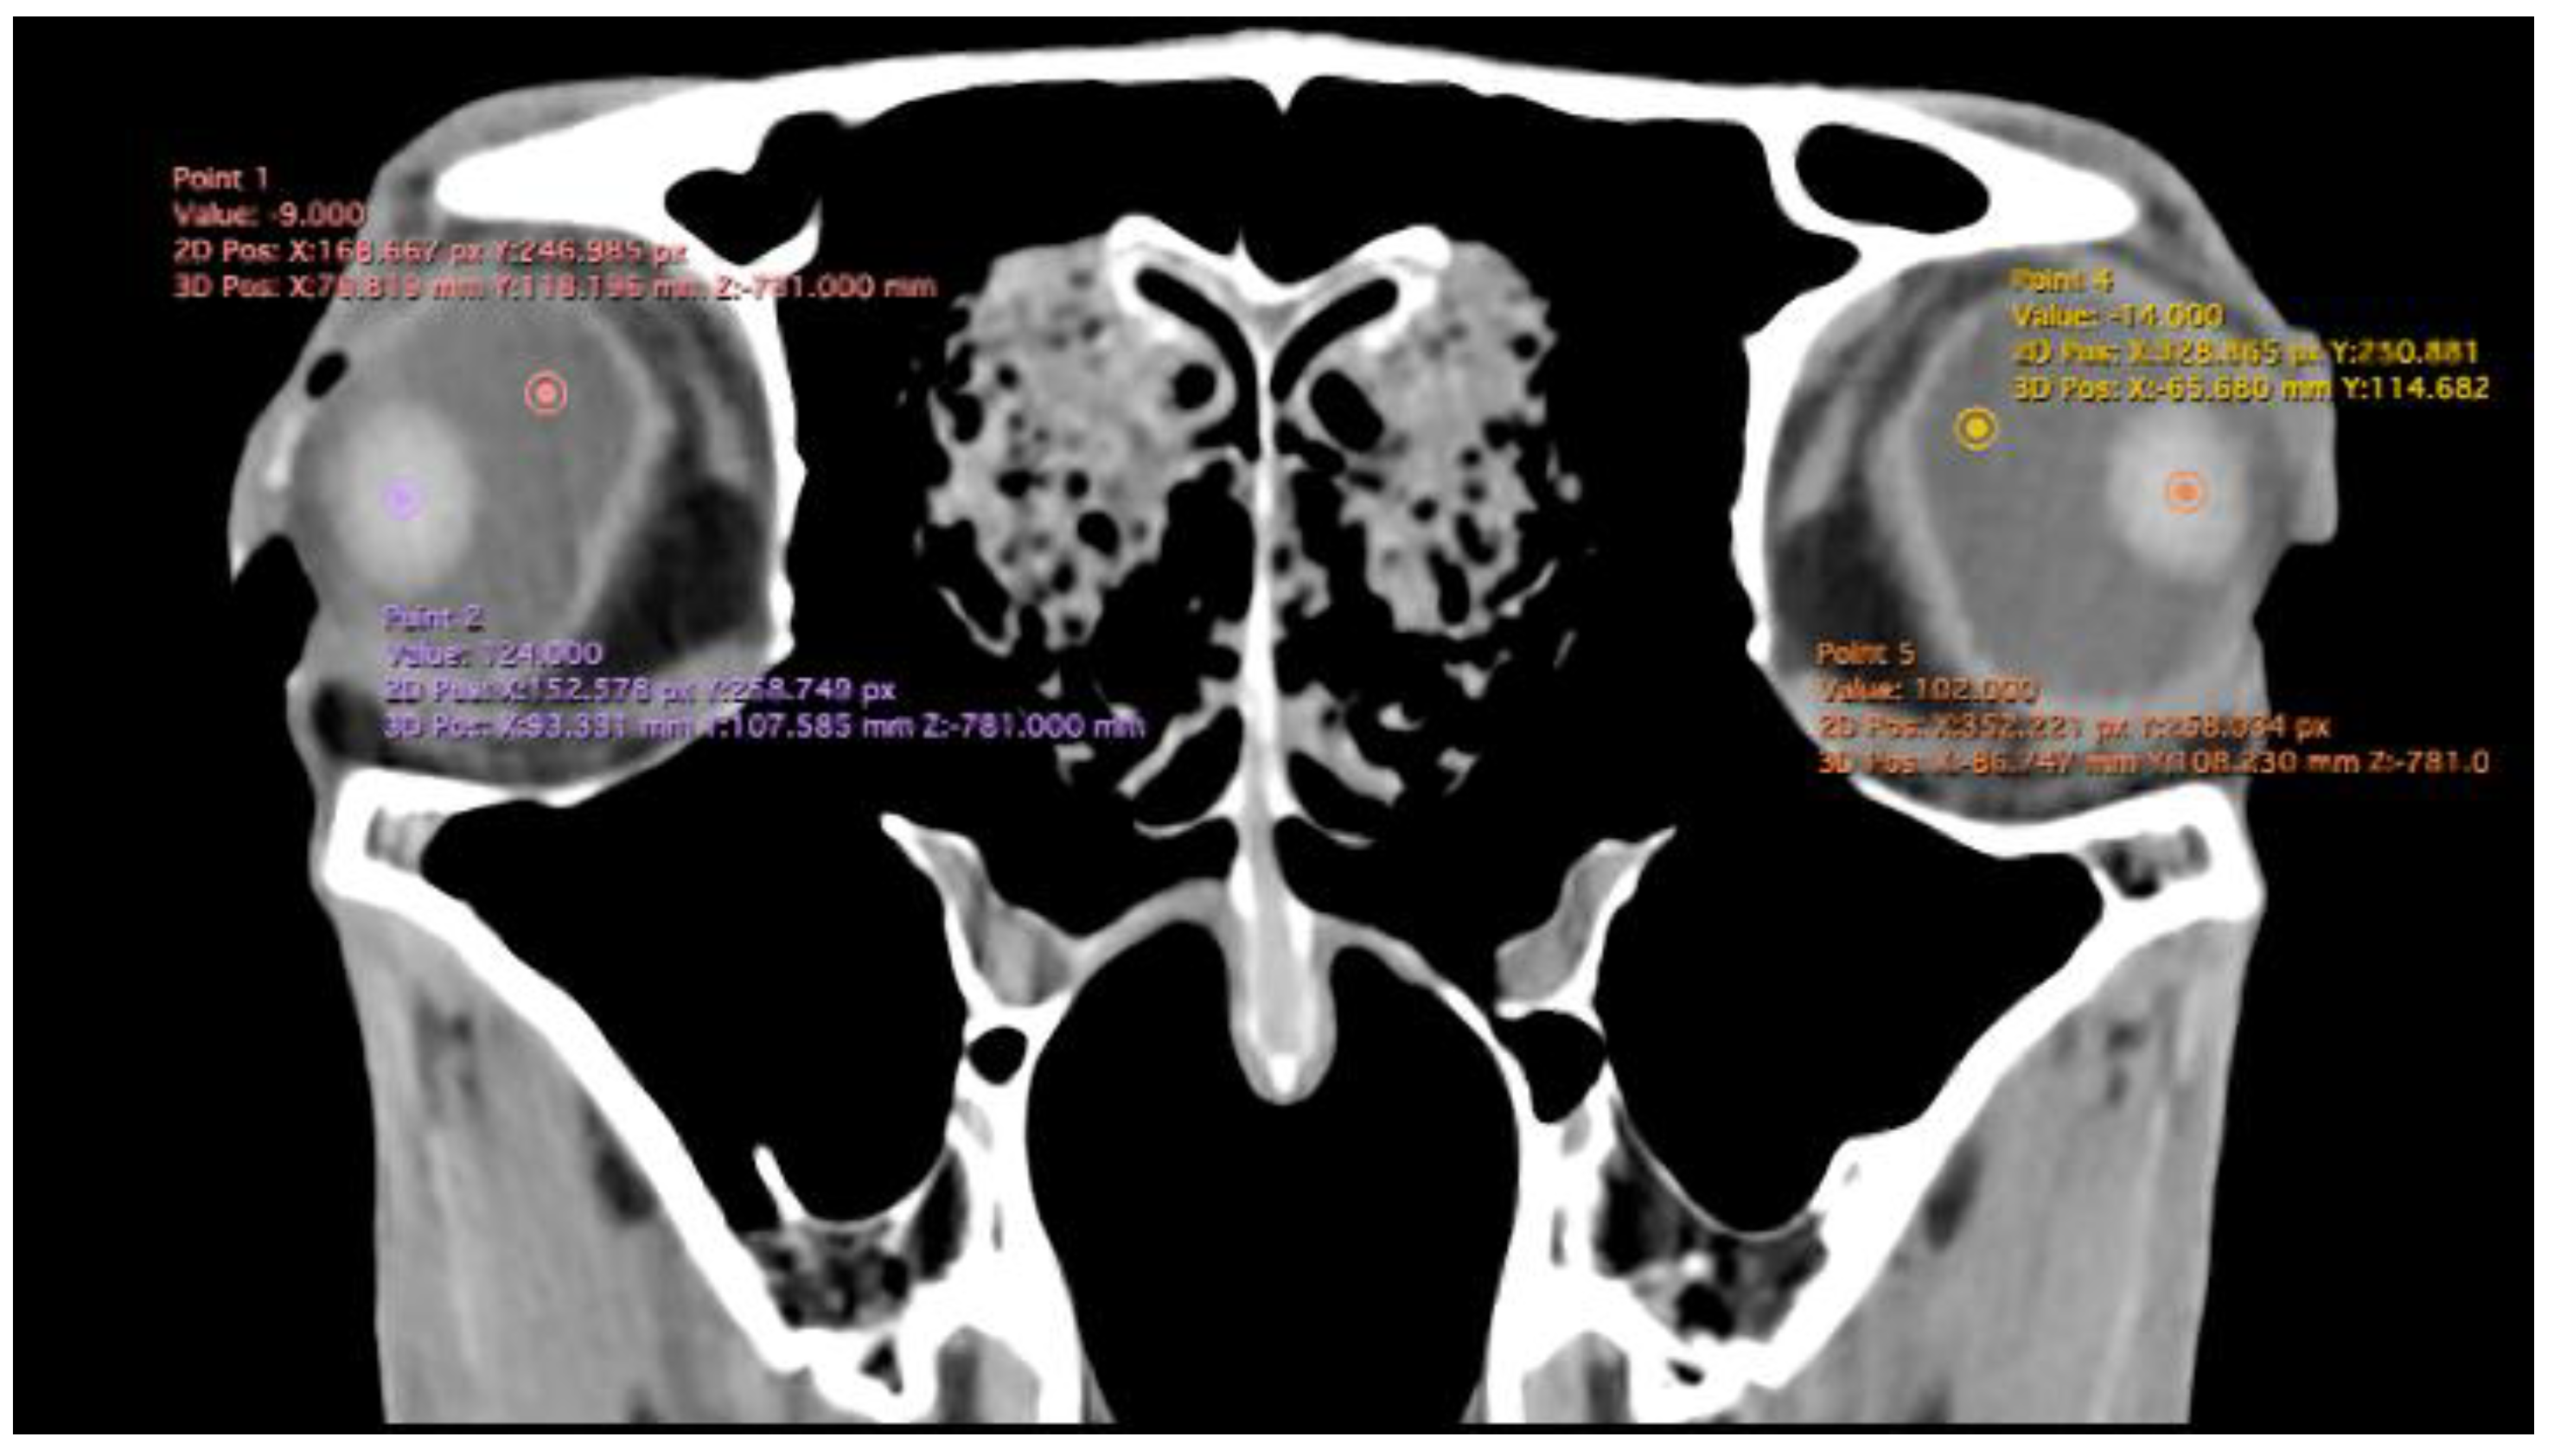

- Anterior chamber, posterior chamber, and lens densities: Attenuation values measured by placing regions of interest (ROIs) centrally in each structure (Figure 3).

| Posterior chamber (UH) | -4.62 | -5.00 | (-8 - -2) | 1.63 | -3.81 | -4.00 | (-7 - -2) | 1.50 | -4.26 | -4 | (-8 - -2) | 1.60 |

| Anterior chamber (UH) | -8.57 | -8.00 | (-14 - -6) | 2.13 | -7.48 | -7.00 | (-13 - -4) | 2.02 | -8.05 | -8 | (-14 - -4) | 2.12 |

| Lens (UH) | 129.62 | 129.00 | (113 - 147) | 7.41 | 128.43 | 129.00 | (101 - 139) | 7.62 | 124.93 | 129 | (101 - 147) | 7.45 |